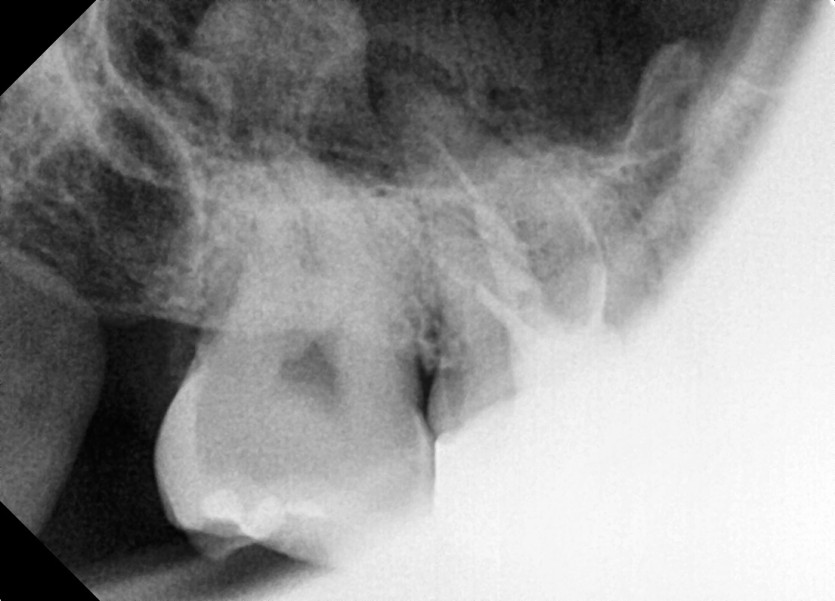

#18,48 사랑니 발치

구강 외과 전문의가 당일 발치했습니다.